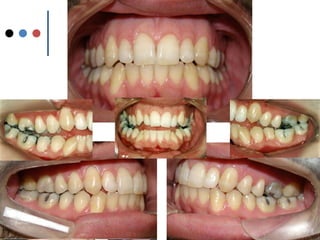

O documento apresenta registros odontológicos de um paciente ao longo de vários anos, incluindo panorâmicas iniciais e subsequentes, remodelações de arcadas dentárias superiores e inferiores ao longo de 7 meses, vedamentos labiais e registros de máxima intercuspidação e guias caninas nas datas listadas.